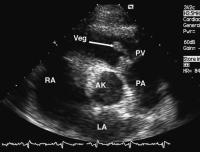

Abbildung 4: Kurze Achse in Höhe der Herzbasis: Von der Pulmonalklappe (PV) ausgehend, finden sich mehrere große Strukturen, Vegetationen (Veg), welche in den rechtsventrikulären Ausflußtrakt flottieren; AK = Aortenklappe, LA = linker Vorhof, PA = Pulmonalarterie, RA = rechter Vorhof

Keywords: EchokardiogrammEchokardiographieEndokarditisHerzKardiologiekurze AchsePulmonalklappe